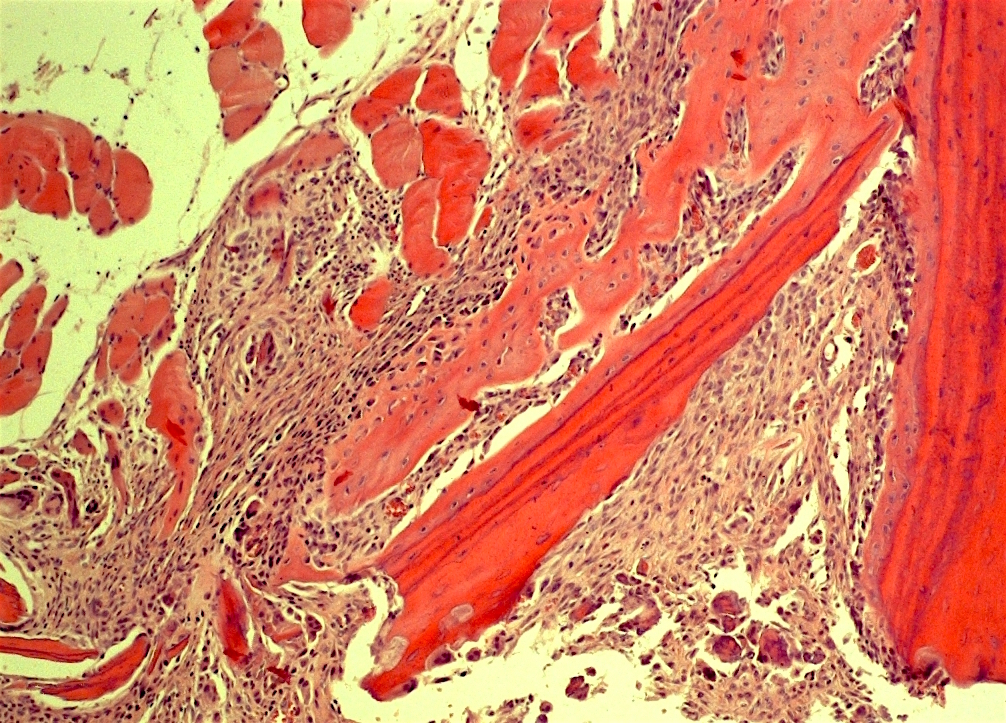

Трансплантируемый в соединительную ткань фрагмент кости, который был предварительно декальцинирован, быстро заморожен и обезвожен в большинстве случаев индуцирует эктопическое костеобразование.

Самое главное чтобы в трансплантат врастали сосуды.

Пусть даже самых мелкий из капилляров будет в этой области, на нем начнут образовываться вытянутые клетки - периваскулярные.

Было доказано что осколки живой кости можно использовать для организации небольших центров остеогенеза и в 1972 году Хэм и Гордон сравнили осколки живой кортикальной кости подсаженные в мышцу и трижды замороженные и оттаявшие, чтобы убить все клетки.

Во втором случае образования кости не происходило.

Она образуется от осколков с живыми остеоцитами.

Губчатая кость имеет много остеогенных клеток, а кортикальная нет.